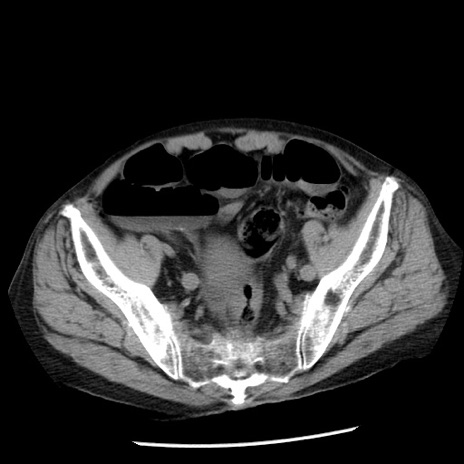

症例26(横断像)

【症例】80歳代男性

【主訴】嘔吐

【現病歴】昨晩2回嘔吐あり、今朝になっても嘔吐あり。来院。

【既往歴】胃潰瘍

【身体所見】意識清明、BT 37.6℃、BP 166/95mmHg、HR 100bpm、SpO2 97%、腹部:平坦・軟、腸蠕動音聴取良好、圧痛なし。

【データ】WBC 21900、CRP 1.46